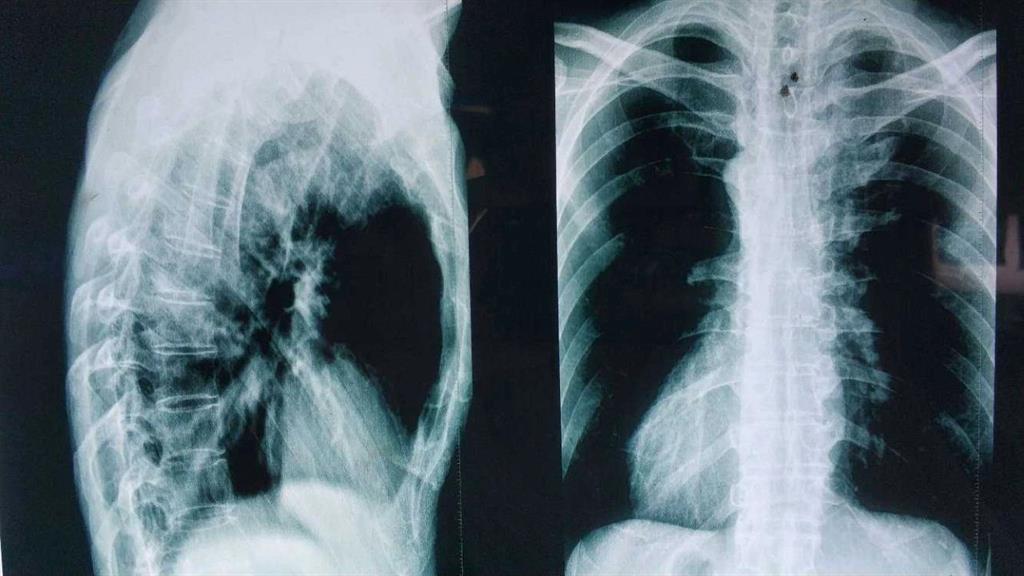

“小伙子!因?yàn)槟阏f拍片是為了確實(shí)是否為強(qiáng)直性脊柱炎,我們剛才在拍片的時候發(fā)現(xiàn)按照那邊醫(yī)生要求的部位拍攝還是看不到病癥點(diǎn),所以我們給你拍了兩次,你到時候給醫(yī)生看的時候都給他看。”

“確實(shí)挺快的,那邊的醫(yī)生給我拍了兩次你看看。”

“這種拍多了就只是花錢多而已。”男孩沒有說話。

醫(yī)生對著拍好的片子來來回回看了好幾遍,男孩就一直站在他邊上,他知道醫(yī)生接下來說的話將決定自己的一生。